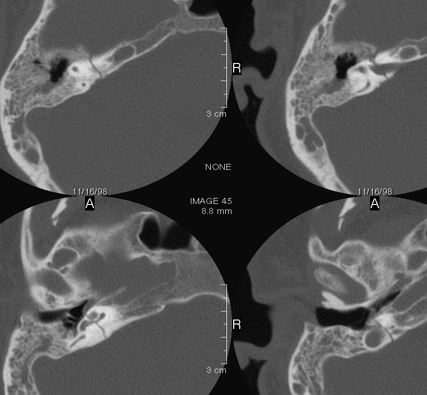

Right Temporal Bone

The external auditory canal shows abnormal soft tissue thickening.

The roof of the mastoid and/or middle ear is fractured.

A possible meningocele and/or encephalocele or CSF leak is present.

The ossicles, in particular the incus long process, the incudostapedial joint and stapes are fractured or dislocated.

The facial canal including the labyrinthine, tympanic and descending portions and nerve are fractured.

The inner ear including the lateral semicircular canals, vestibule and/or cochlea is fractured or otherwise abnormal.

There is subperiosteal, epidural or subdural hematoma along the roof of the mastoid or middle ear or the superior and posterior (intracranial) surfaces of the petrous portion of the temporal bone.

Left Temporal Bone